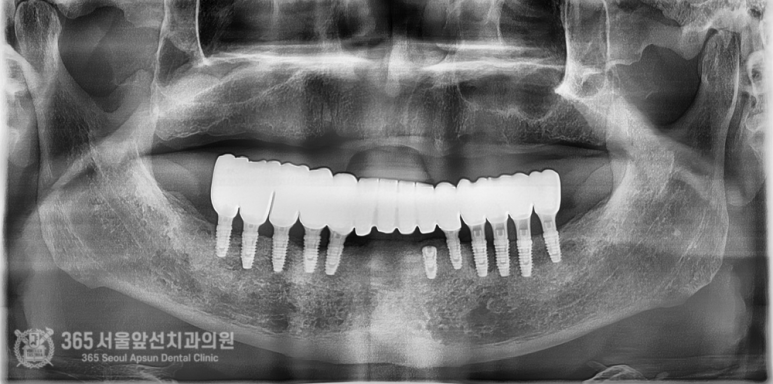

촬영일시 2024.09.01. 내원 당시 술전 파노라마 엑스레이 사진입니다. 환자분 안모 기준으로 좌측 작은 어금니 부위(#24,25번 치아 부위)를 제외한다면 뼈의 상태를 수술하기에 양호한 편에 속합니다. (저희는 이런 경우를 운동장 같은 뼈라고 비유하곤합니다 ㅎㅎ) 촬영일시 2024.11.01. 좌우측 어금니 부위에는 상악동거상술(수직접근법)을 동반하여 임플란트를 심어드렸구요. 앞니 부위는 뼈이식을 통해 뼈의 두께를 늘려드렸습니다. 처음 말씀드렸던 환자분 기준 왼쪽 작은 어금니 부위(#24,25 치아 부위)에도 뼈이식을 충분히 하여 골재생을 도모했습니다. 가이드나 스탠트의 도움이 전혀 없이 상악동 거상술 및 골이식을 포함하여 임플란트 9개를 식립하는데 대략 40분이 좀 안걸렸습니다. 임플란트간 위치와 기울기가 보기 좋게 식립되었습니다 ㅎㅎ (매일매일 하다보면 수술이란게 환자분들 걱정만큼 오래 걸리지 않습니다 ㅎㅎ) 임플란트가 좋은 위치에 식립되고 잘 완성된 모습입니다. 촬영일시 2024.12.10. 환자분께선 걱정을 많이 하셨는데 순식간에 끝났다며 좋아하셨습니다 ㅎㅎ 상악동 거상술 부위와 골이식 부위가 단단하게 굳는 기간 동안 무리하지 않도록 주의를 당부드렸습니다.